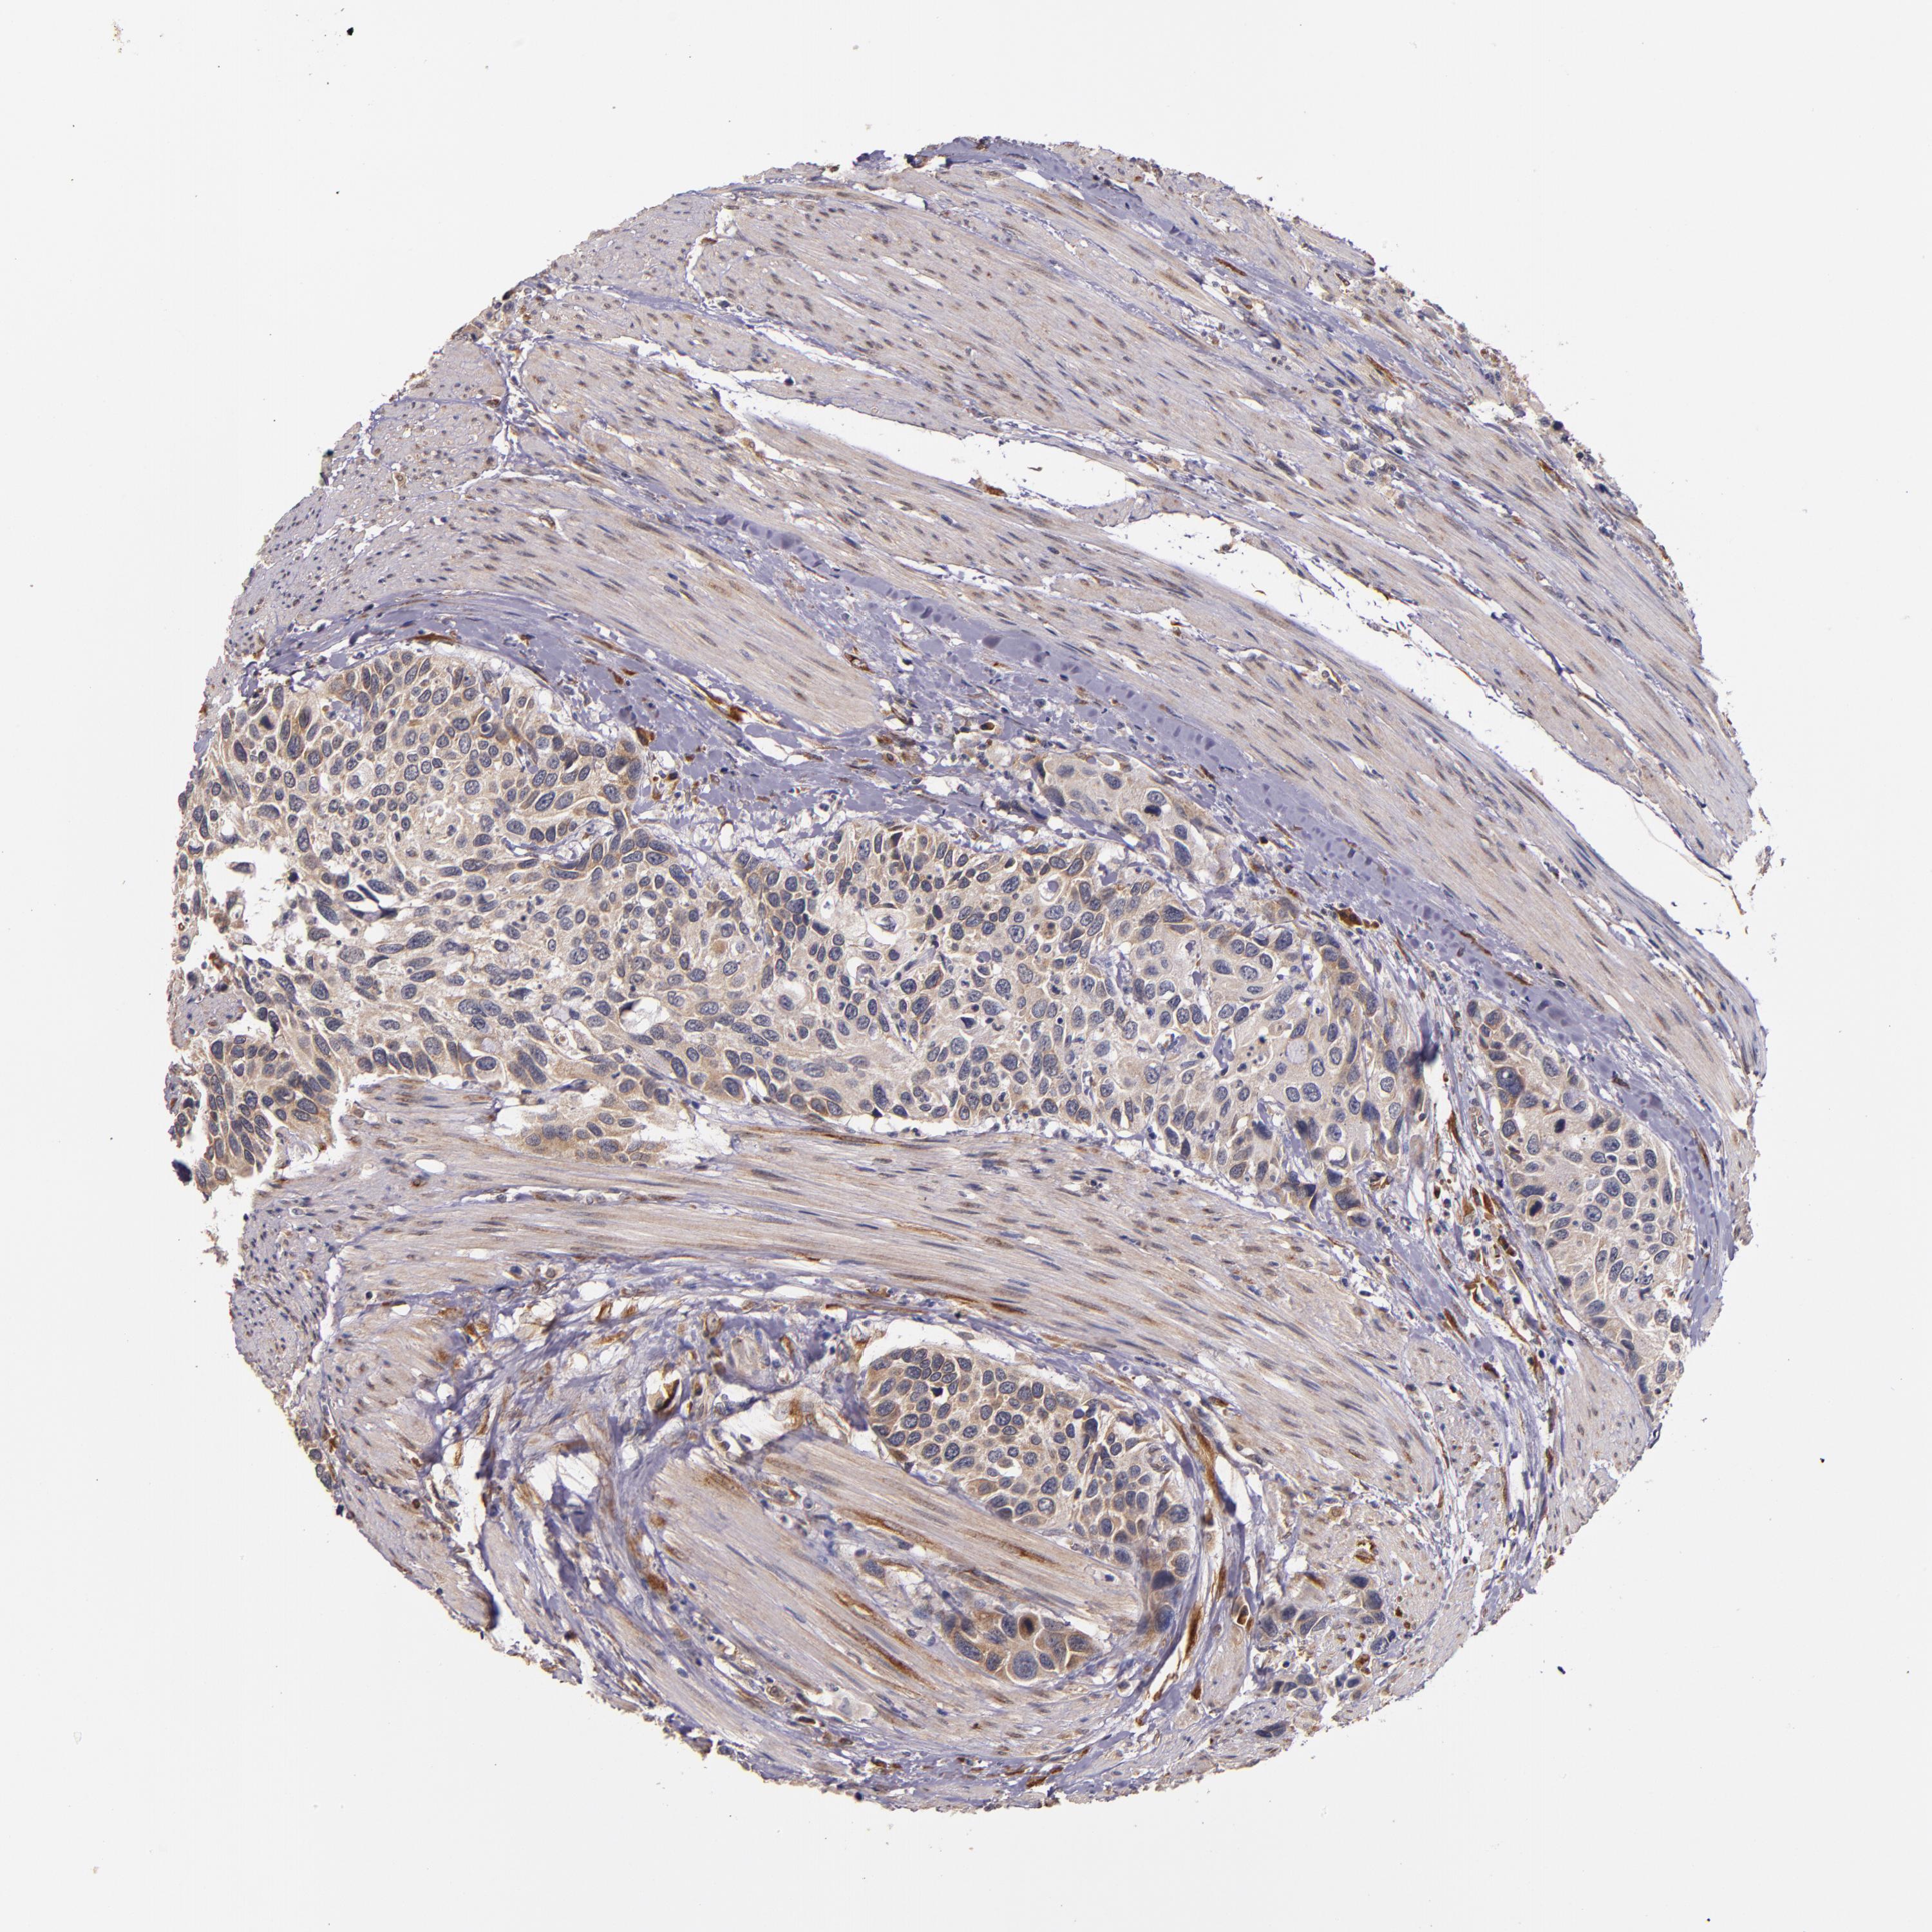

UROTHELIAL CANCER - Protein expressioni

A mouse-over function shows sample information and annotation data. Click on an image to view it in a full screen mode. Samples can be filtered based on level of antibody staining by selecting one or several of the following categories: high, medium, low and not detected. The assay and annotation is described here.

Antibody stainingi

Antibody staining in the annotated cell types in the current human tissue is reported as not detected, low, medium, or high, based on conventional immunohistochemistry profiling in selected tissues. This score is based on the combination of the staining intensity and fraction of stained cells.

Each image is clickable and will lead to virtual microscopy that enables deeper exploration of all samples and also displays staining intensity scores, fraction scores and subcellular localization as well as patient and tissue information for each sample.

Antibody HPA002859

Antibody CAB011655

Urothelial carcinoma, High grade

Urothelial carcinoma, Low grade

Adenocarcinoma, NOS